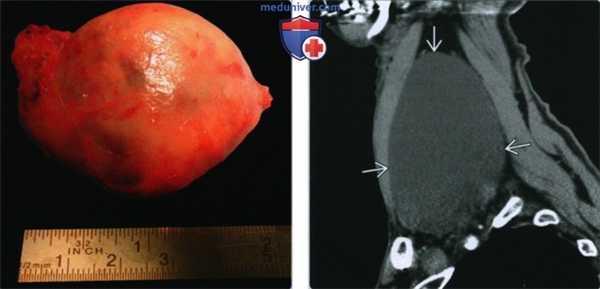

(Слева) Макропрепарат лимфоцеле. Видно наличие характерной капсулы. Образование обычно легко удаляется хирургически, после чего не рецидивирует.

(Справа) КТ с КУ, сагиттальная проекция. Характерная картина лимфоцеле: однодольчатое образование округлой или овальной формы, лишенное перегородок, имеющее жидкостную плотность. Располагается киста в надключичной ямке, не накапливает контраст и не имеет различимых стенок.